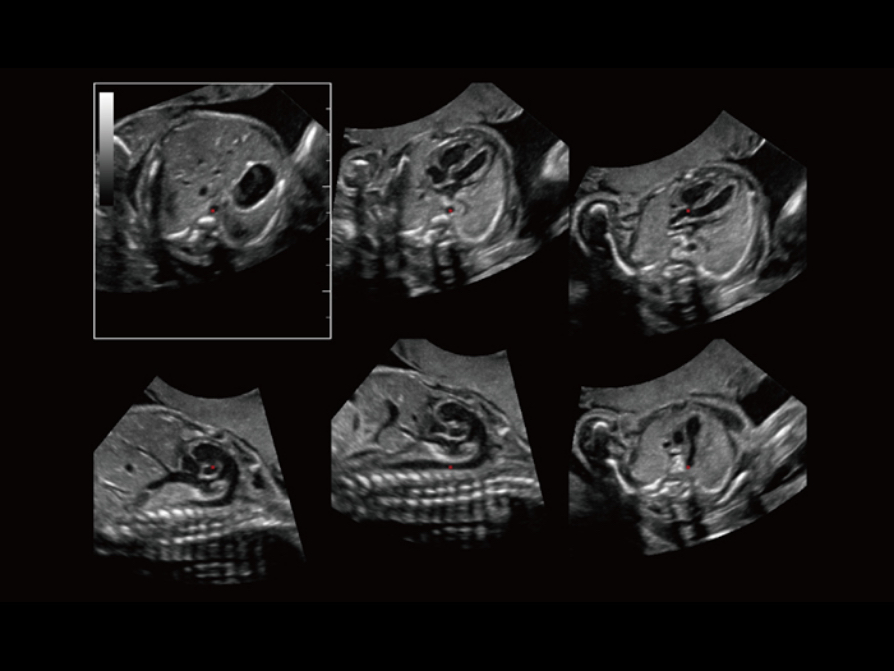

The new Resona series with Zone Intelligence has further extended the capability of Smart Planes for intelligent fetal heart diagnosis. With extremely simple user-interaction of defining one point, it allows fully automatic and accurate detection of the six most important fetal cardiac planes. In addition, it helps standardize the orientation of the fetal heart images, and therefore improving the efficiency and effectiveness of fetal heart diagnosis.